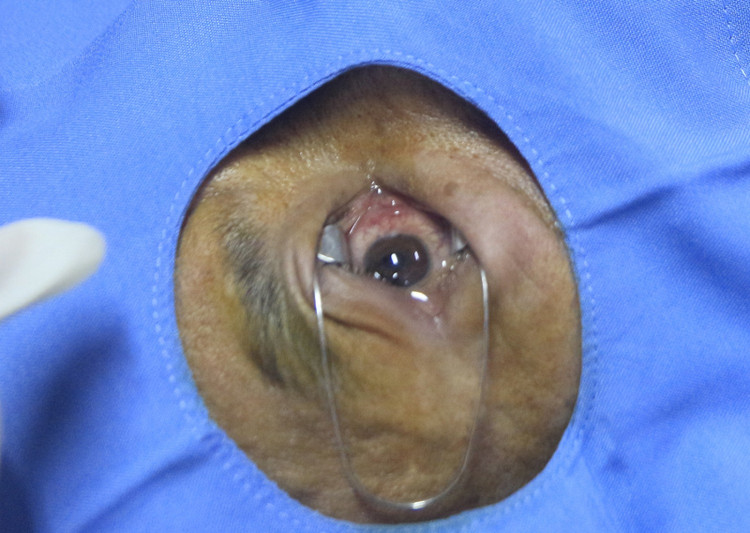

Ekip phẫu thuật do Ths. BS Nguyễn Hải Dương – Trưởng Khoa Mắt xử trí tổn thương xé rách nhãn cầu cho bệnh nhânEkip phẫu thuật do Ths. BS Nguyễn Hải Dương – Trưởng Khoa Mắt xử trí tổn thương xé rách nhãn cầu cho bệnh nhân

Ekip phẫu thuật do ThS.BS Nguyễn Hải Dương, Trưởng Khoa Mắt, Bệnh viện Bãi Cháy đã tiến hành phẫu thuật xử trí tổn thương, bảo tồn nhãn cầu. Quá trình phẫu thuật kiểm tra bệnh nhân có vết rách giác mạc cạnh trung tâm từ 7h-11h, bờ nham nhở, dải xuất tiết sau mép rách, mống mắt dính mặt sau vết rách, đồng tử giãn, phản xạ ánh sáng yếu.

Các bác sĩ đã tiến hành làm sạch vết rách, lấy bỏ dị vật và khâu giác mạc, tiêm kháng sinh tiền phòng, bảo tồn nhãn cầu, kháng độc tố uốn ván. Hiện tại, tình trạng sức khỏe bệnh nhân ổn định, tiếp tục được điều trị kháng sinh, chống viêm.